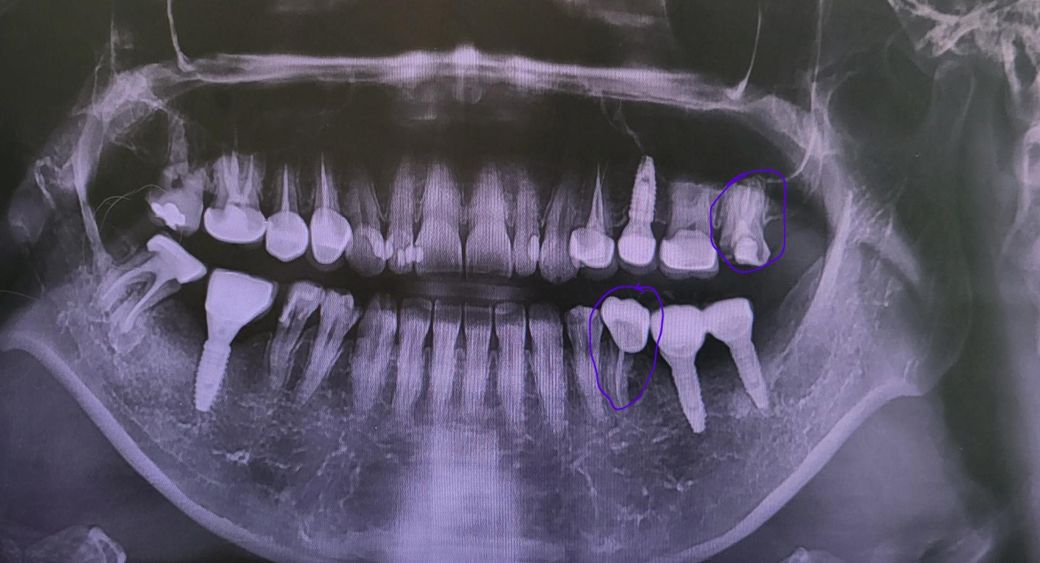

예전에 이 했던 데가 떨어져서 어제 치과을 갔는데요 원장님이 치아가 많이 썩었다고 못 살린다고 뽑아야 한다고 하시더라고요ㅜㅜ 그래서 뽑았는데 뽑을 때도 오래 걸렸어요ㅠㅠ 왼쪽 위 끝 어금니 데요 발치해서 뻥 뚫여있어요ㅜㅜ 일주일 지나면 괜찮아진다고 하시는데ㅠㅠ 임플란트 해야 하냐고 물으니 생활해 보고 불편하면 하고 안 불편하면 안 해도 된다고 하시더라고요.. 근데 집에 와서 보니 만약에 안 불편해서 안 하면은 아래쪽 어금니가 위로 올라오지 않나요? 불편하지 않으면 안 해도 되는지.. 조언 부탁드립니다ㅜㅜ 그리고 왼쪽 아래에서 끝에서 3번째 어금니도 신경까지 다 썩어서 나중에 떨어지면 것도 발치 해야한다고 하시더라고요ㅠㅠ 근데 여기는 임플란트 꼭 해야 한다고 하셨어요😭

상태 안좋은 치아들이 몇개 더 있네요

왼쪽 위 제일 끝치아는 맞닿는 치아가 임플란트이므로 빈공간이 있더라도 임플란트가 올라오진 않습니다 그래도 다른 어금니들의 교합력 생각하면 임플란트 심어주는게 좋긴하죠